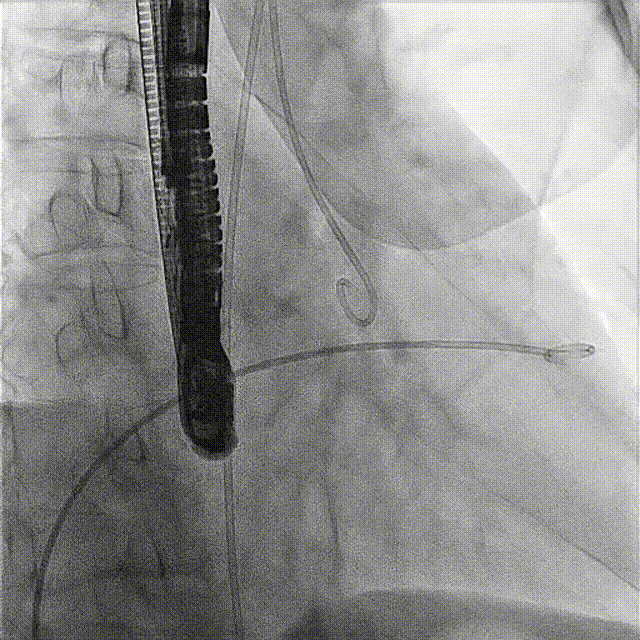

術(shù)前DSA

接受手術(shù)的為一名80歲男性,因“心悸2年,氣喘伴下肢水腫半年”入院。超聲心動(dòng)提示“極重度三尖瓣反流,右房及右室明顯擴(kuò)大,右心收縮功能輕度減低,左心收縮功能正常,肺動(dòng)脈壓力正常”?;颊咄瑫r(shí)合并有“持續(xù)性房顫”及“慢性心力衰竭”,病史持續(xù)2年,規(guī)律口服抗凝及強(qiáng)心、利尿治療治療效果不佳,癥狀持續(xù)。經(jīng)廈心心臟團(tuán)隊(duì)評(píng)估后,認(rèn)為患者三尖瓣極重度反流并伴有心衰表現(xiàn),長(zhǎng)期內(nèi)科藥物治療效果不佳,且患者高齡、外科手術(shù)風(fēng)險(xiǎn)高,因此決定采用微創(chuàng)經(jīng)頸靜脈LuX-Valve Plus三尖瓣置換系統(tǒng)為患者治療。